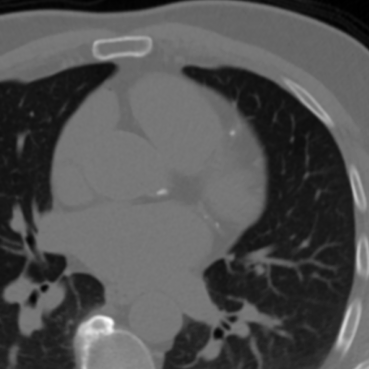

The effectiveness of our label-guided approach is visualized in Figure 4, which compares feature representations generated by standard DINO and DINO-LG models via PCA analysis. The figure shows an original CT slice containing coronary calcification in the left anterior descending artery (a), where the ground truth annotation (b) occupies approximately 0.04% of the image area. Standard DINO features (c) exhibit diffuse activation across cardiac structures, while DINO-LG features (d) demonstrate concentrated activation on calcified regions (bright yellow areas), validating successful feature guidance toward regions of clinical interest. The PCA visualization is applied to 768-dimensional [CLS] token embeddings extracted from the final transformer layer to illustrate how label-guided training directs the model’s attention to task-relevant features.

Refer to caption

(a)

(b)

(c)

(d)

Figure 4: Feature visualization comparison via PCA. (a) Original CT slice. (b) Ground truth annotation. (c) Standard DINO features. (d) DINO-LG features.